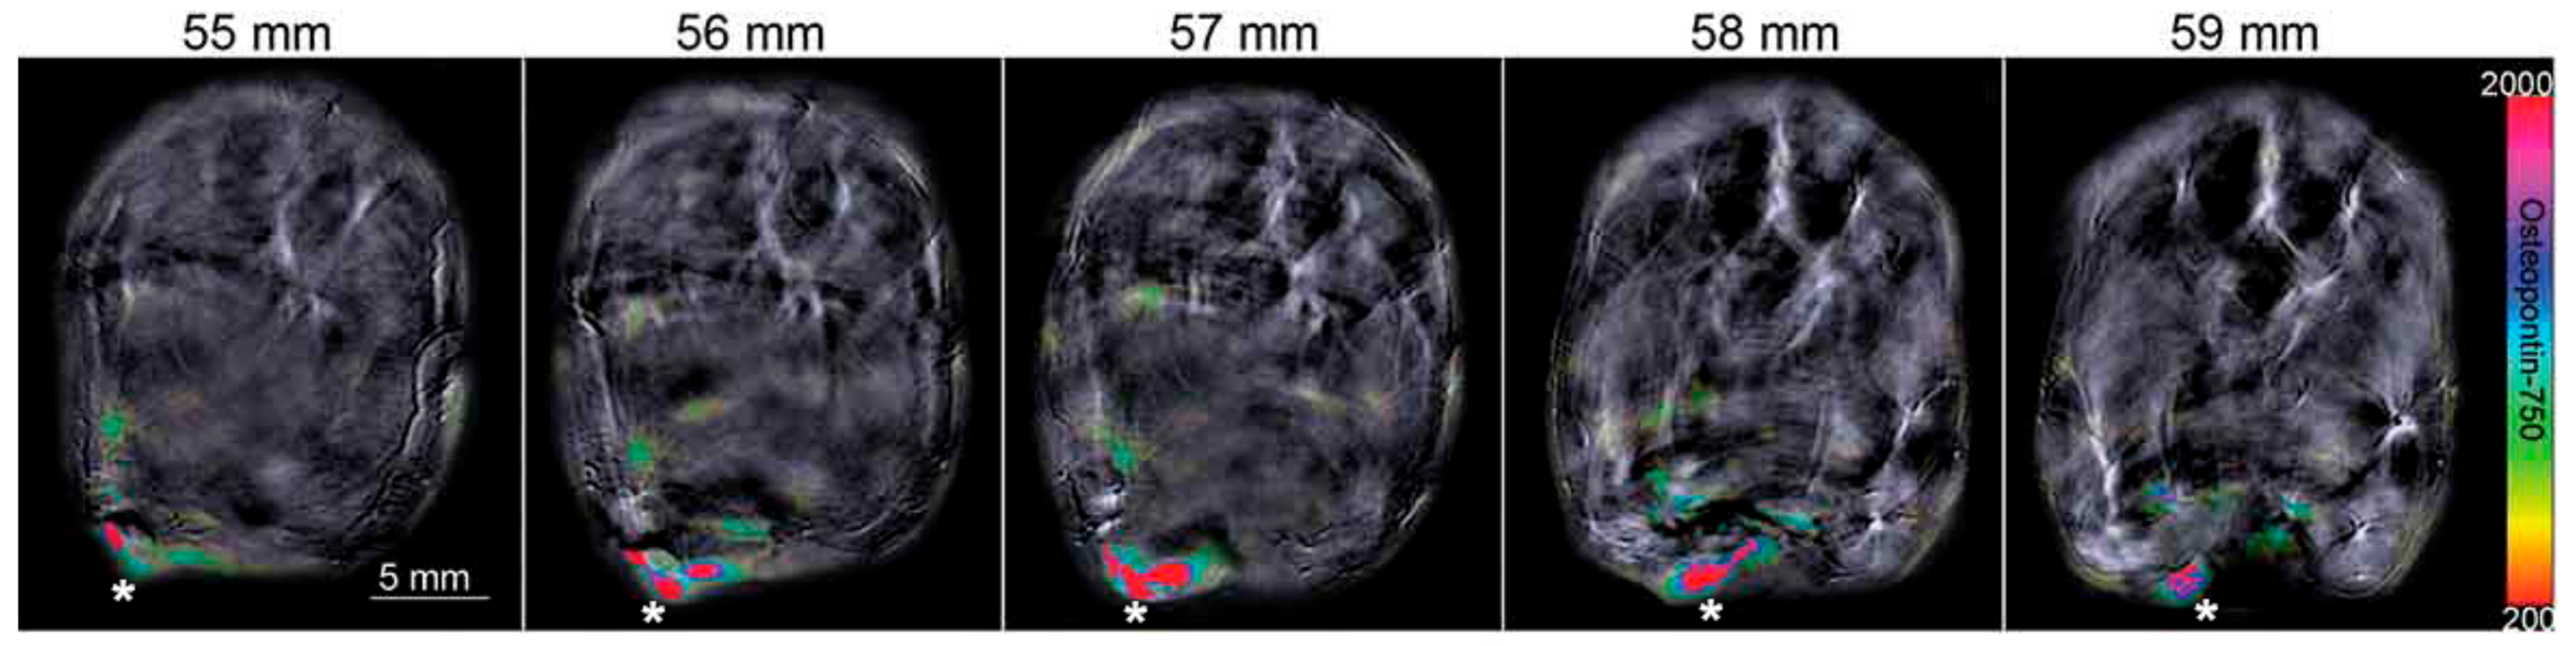

- Samykutty, A.; Thomas, A.; McNally, M.; Chiba, A.; McNally, L.R. Osteopontin-targeted probe detects orthotopic breast cancers using optoacoustic imaging. Biotech. Histochem. 2018, 93, 608–614. [Google Scholar] [CrossRef] [PubMed]